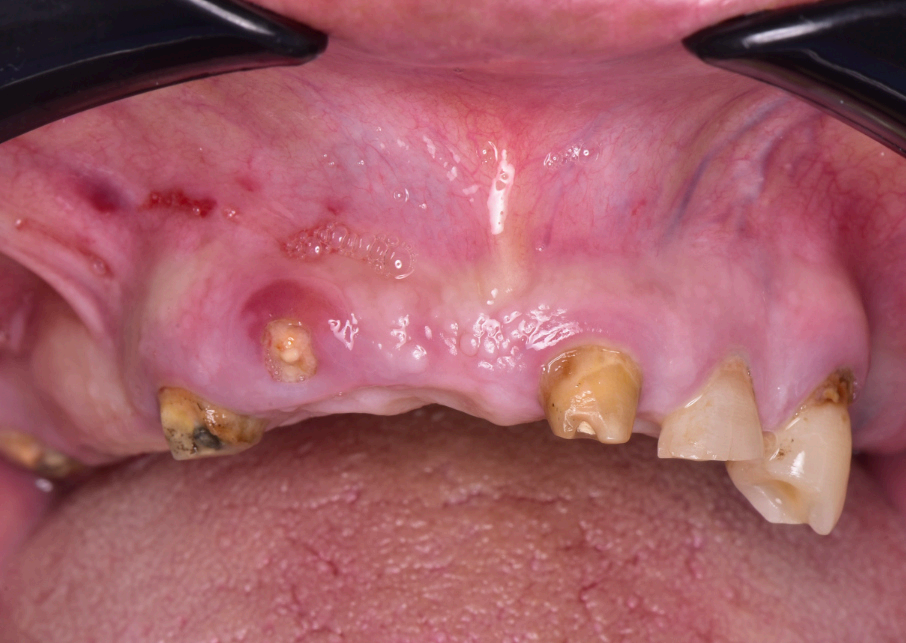

Preoperative and Planning •Fig. 1.1: Frontal intraoral view of the maxilla showing residual roots and fractured teeth. •Fig. 1.2: Occlusal intraoral view highlighting the compromised dentition. •Fig. 1.3: Digital wax-up integrated with a 3D facial scan and smile design guidelines. •Fig. 1.4, 1.5: Visualization of implant positions (16, 14, 12, 22, 24, 26) on a 3D model, prosthetically driven placement. •Fig. 1.6: 3D rendering of the wax-up aligned with the bone level, illustrating bone-prosthesis relationship.

The patient, a 70-year-old female, presented to the dental clinic with a chief complaint of compromised maxillary dentition and a desire for a fxed, aesthetically pleasing rehabilitation. Her medical history was unremarkable, with no systemic diseases, allergies, or medications reported, and her general health was deemed excellent for her age. Intraoral examination revealed a partially edentulous maxilla with failing dentition: residual roots were present at positions 13 (upper right canine) and 21 (upper left central incisor), while teeth 22 (upper left lateral incisor) and 13 exhibited fractures rendering them non-restorable (Fig. 1.1, 1.2). The patient expressed a strong preference for a fxed prosthesis that would restore both function and aesthetics, with a natural gingival contour as a priority.

Initial diagnostic workup included a comprehensive radiographic evaluation using cone-beam computed tomography (CBCT) to assess bone volume and quality at the proposed implant sites: 16 (upper right frst molar), 14 (upper right frst premolar), 12 (upper right lateral incisor), 22 (upper left lateral incisor), 24 (upper left frst premolar), and 26 (upper left frst molar). The CBCT confrmed suffcient bone height and width to support six implants without the need for extensive grafting, though minor bone leveling was anticipated. Digital impressions were acquired using the Shining3D Elite intraoral scanner, capturing detailed surface anatomy of the maxilla and remaining teeth. A 3D facial scan was also performed to integrate smile design principles, ensuring the prosthetic outcome aligned with the patient’s facial aesthetics (Fig. 1.3). A digital wax-up was created in Exocad, simulating the fnal prosthesis with attention to tooth proportions, midline alignment, and lip support. After patient approval, this wax-up served as the foundation for implant planning (Fig. 1.4, 1.5).

The surgical procedure was performed under local anesthesia in a single session. The residual roots at 13 and 21, along with the fractured teeth at 22 and 13, were extracted with minimal trauma to preserve the surrounding bone and soft tissue. The stackable guide was secured intraorally using the fxation bar anchored to the maxilla, providing a stable reference for implant placement (Fig. 2.2). Osteotomies were prepared at the planned sites (16, 14, 12, 22, 24, 26) using the guide’s drilling sleeves, ensuring accuracy in depth and angulation. Six implants were inserted, and multi-unit abutments (MUAs) were immediately placed to facilitate prosthetic connection (Fig. 2.3).